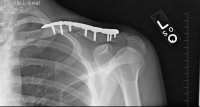

Xrays

Update: August 23, 2010

Saw the Doc again, he's pleased with the results, but it's just going to take more time. If you look at the x-rays you can see that the void is closing, slowly.

He seemed very confidant that it should be ok by T-Day, will know more in 6 weeks.